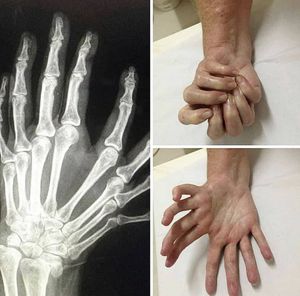

Mirror Hand Syndrome...

Ulnar dimelia, also referred to simply as Mirror hand, is a very rare congenital disorder characterized by absence of radial ray